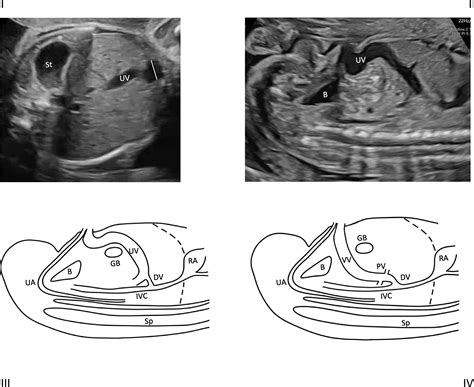

Detection usually occurs during the second or third-trimester anatomy scan. Sonographers look for a fluid-filled, cyst-like structure within the fetal abdomen that shows blood flow when color Doppler ultrasound is applied. Because the structure is vascular, it is easily distinguishable from other fluid-filled cysts (like those in the gallbladder or bowel) once the appropriate imaging techniques are utilized.

• Doppler Flow Studies: These studies measure the velocity and pattern of blood flow through the varix to check for turbulence or restricted flow.